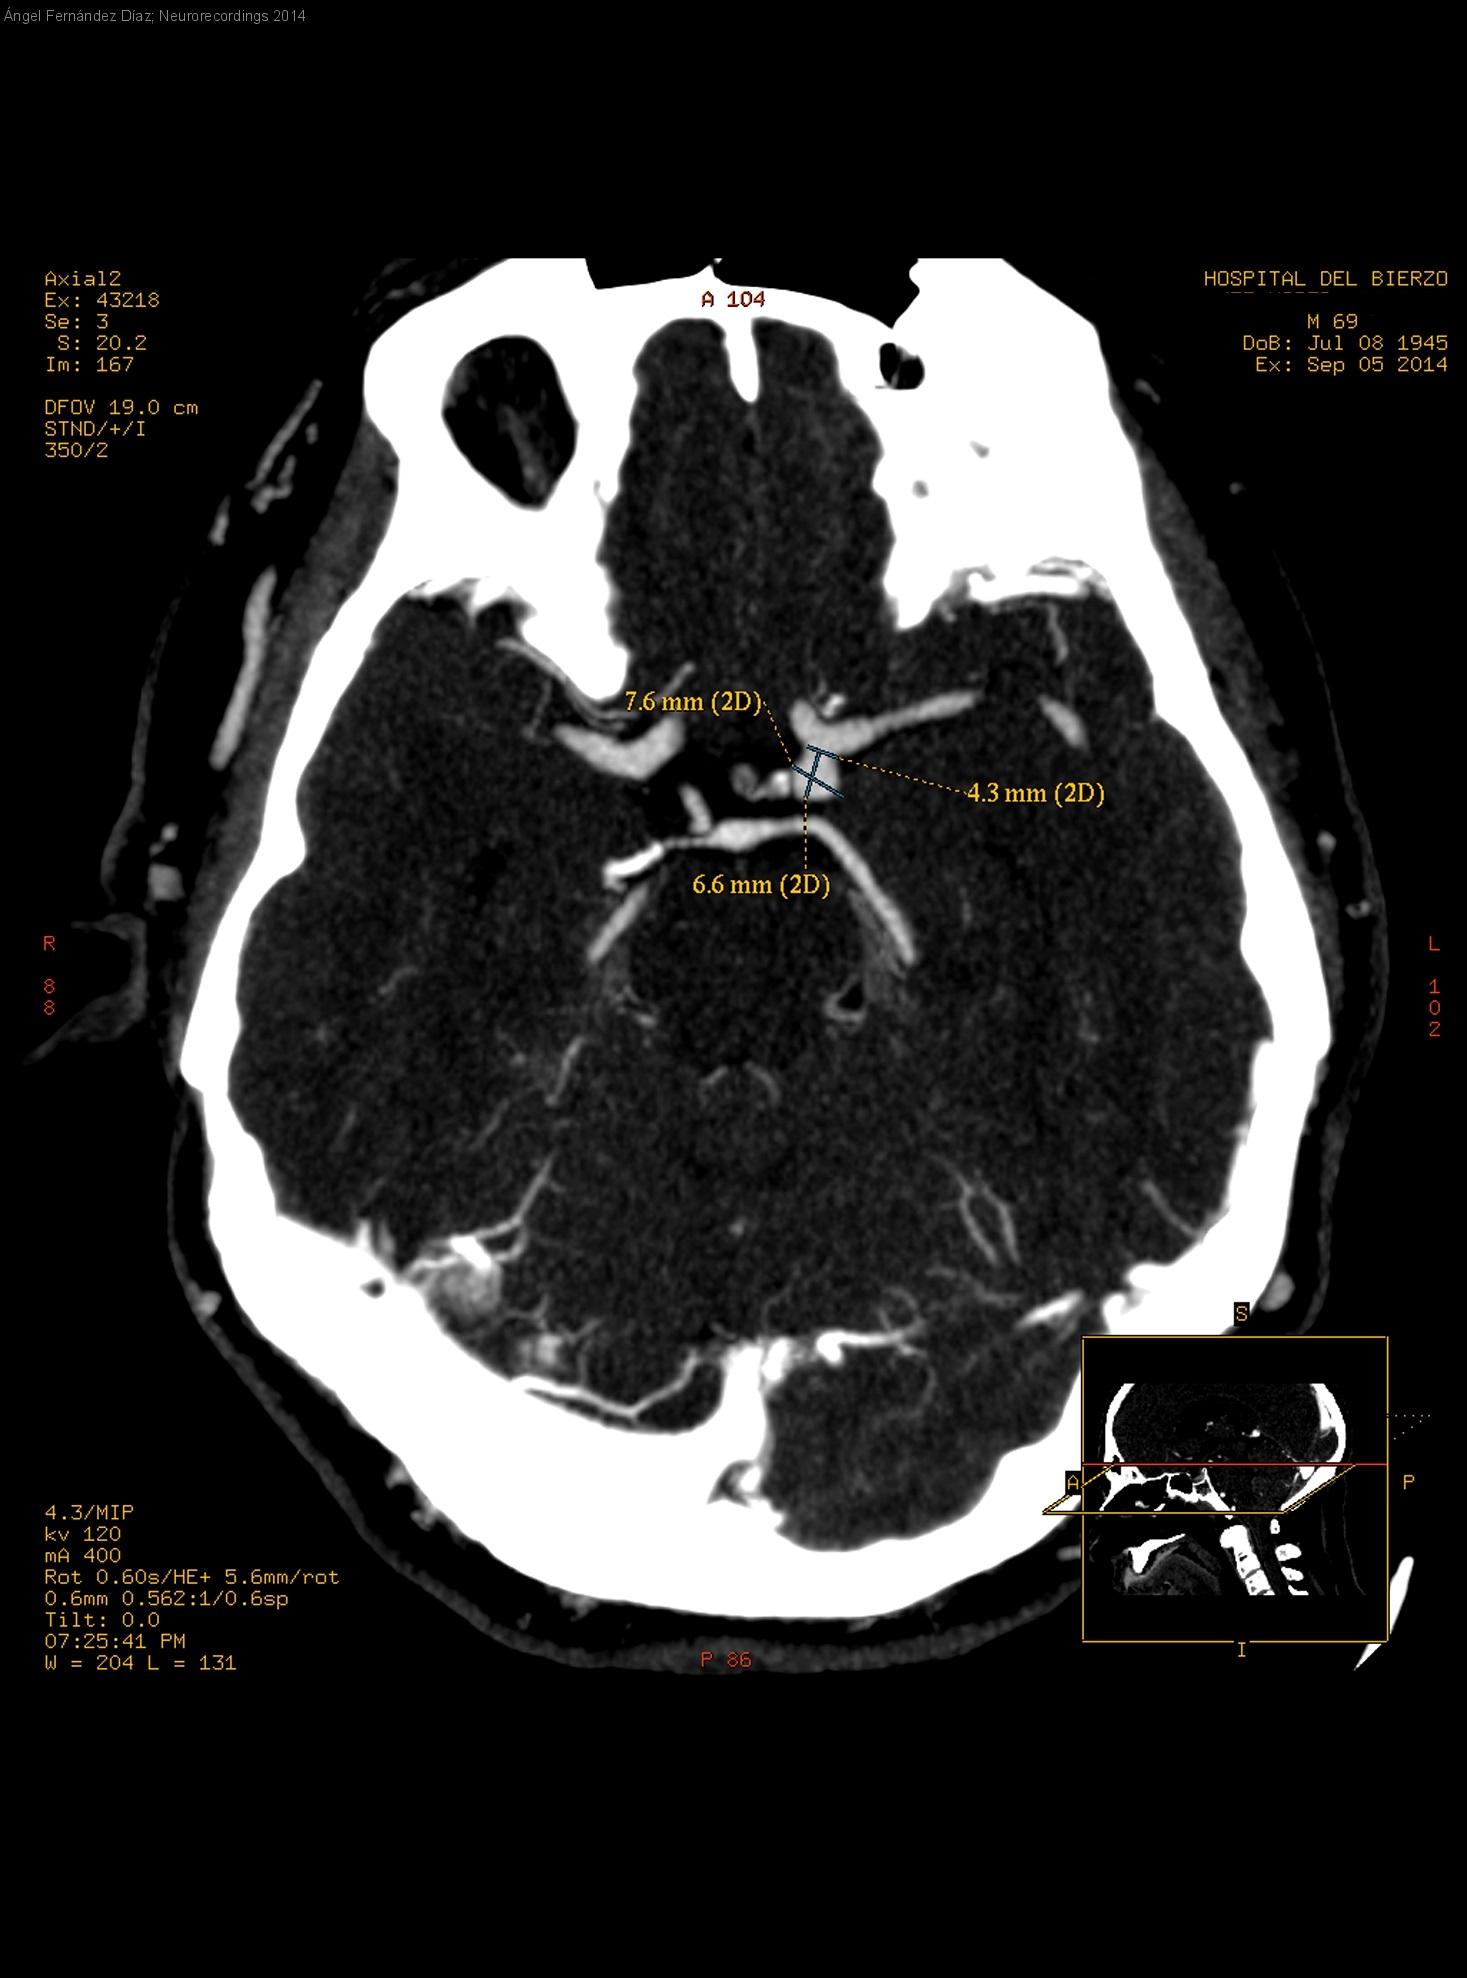

PARÁLISIS SUBAGUDA Y PROGRESIVA DEL TERCER NERVIO CRANEAL IZQUIERDO

Hombre | 69 años

Diagnóstico final: Aneurisma bilobulado ICA-PCoA izquierdas